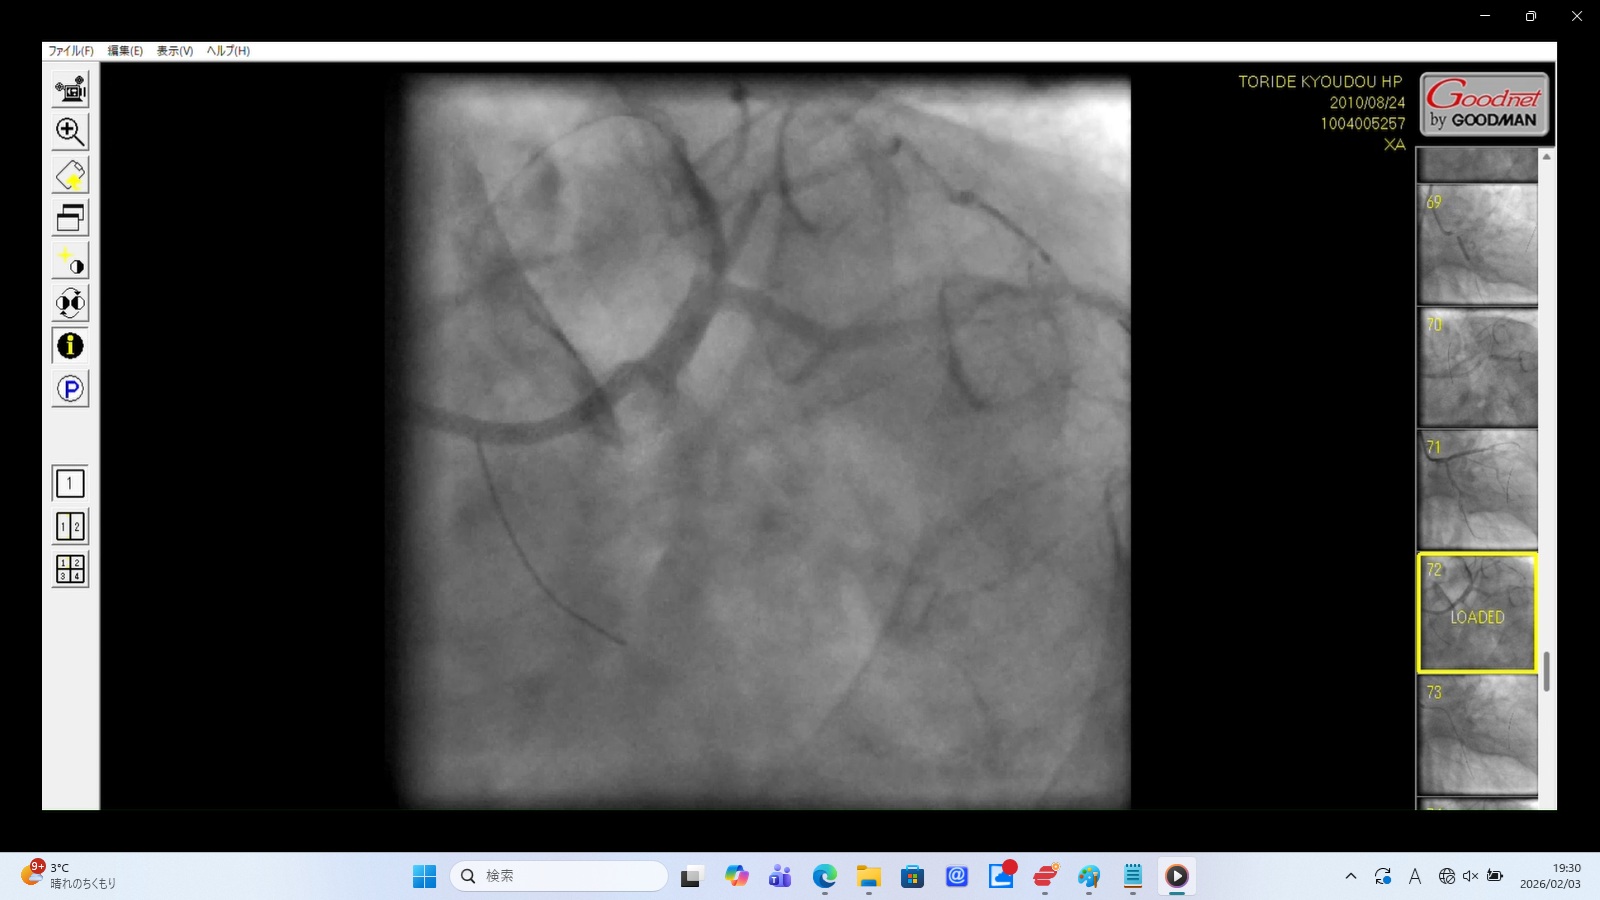

1. The Unidentified Foreign Body (The "Smoking Gun")

Caption: Evidence of Iatrogenic Foreign Body Displacement

Medical Findings:

Cylindrical Radio-opaque Object: A distinct, cylindrical metallic-density object is visible in the upper-right quadrant of the frame.

Synchronous Movement: The object moves rhythmically with the cardiac pulsation, indicating it is located within the thoracic cavity or pericardium.

Significance: This is an unaccounted-for medical device fragment (likely a detached catheter tip or stent). Its presence, combined with the lack of any mention in official medical records or the autopsy report, is irrefutable evidence of a surgical mishap followed by an institutional cover-up.